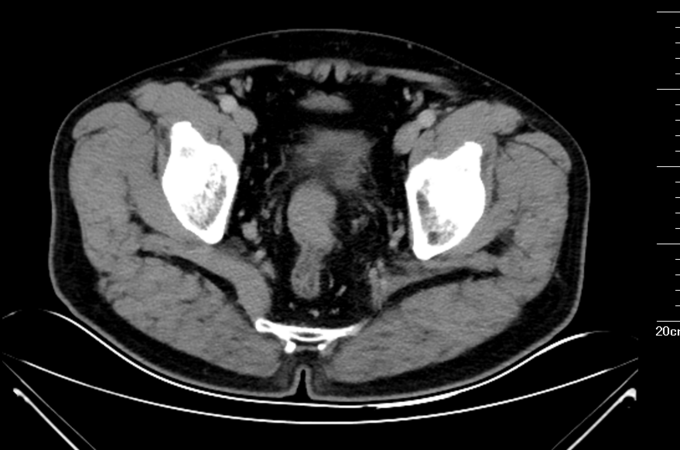

查体:腹平坦,未见胃肠型及蠕动波,未见腹壁静脉曲张。全腹软,未触及腹部肿块,压痛(-),反跳痛(-),肌紧张(-)。肝脾肋下未触及,Murphy’s 征(-),肝区叩击痛(-),移动性浊音(-)。肾区叩击痛(-)。肠鸣音正常,4次/分。肘膝位,肛门进指顺利,进指约7cm,未触及明确肿物,退指指套无染血。 辅助检查:马应龙肛肠医院肠镜检查显示:距离肛门60cm30cm见两枚大小约0.3*0.2cm息肉,表面光滑,广基、无蒂、无色泽略红,距肛门15cm处可见一半环行菜花样粘膜隆起。表面凹凸不平,出血、糜烂与污秽交织在一起,隆起向腔内生长,至管腔狭窄,镜身未通过,取病理5块。 术前腹部CT:乙状结肠下段肠壁增厚